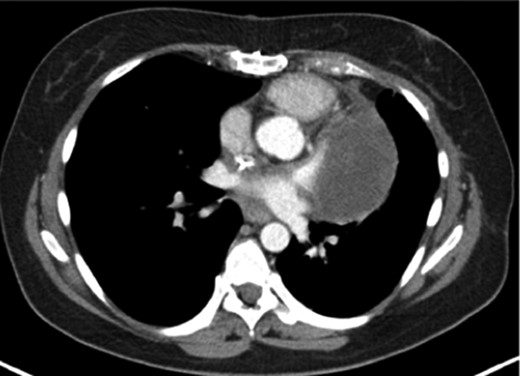

A 48-year-old female presented with progressive dyspnoea, non-productive cough, weakness, dizziness and loss of weight stretching over a period of 4 weeks. The past history was non-specific. Echocardiography revealed a large, intracavitary, broad-based mass attached to the left interatrial wall and the roof of the atrium with extension to the superior pulmonary vein. A left atrial myxoma was suspected. After ruling out an associated coronary heart disease, the patient underwent resection of the atrial septum including the atrial roof with subsequent patch reconstruction of the left atrium and the left upper pulmonary vein. Histologically, the tumour had a myxoid background with spindle-shaped cells, moderate cellularity and atypia (Fig. 1A). There were no definitive areas of vascular patterns. Based on these histological findings and the preoperative imaging, a diagnosis of myxoma was presumed and subsequently no further immunohistological staining was carried out. No further adjuvant therapy was performed. Regular follow-up in an interdisciplinary team included clinical evaluation, chest-CT and echocardiography at a 6-month interval. At 14 months, evidence of local recurrence was observed. An open biopsy was performed and compared with the initially resected specimen (Fig. 1B). The diagnosis of myxosarcoma was confirmed. Following four cycles of neoadjuvant chemotherapy with iphosphamide and doxorubicin, the patient underwent a complete en bloc resection of the tumour mass including a left pneumonectomy due to massive infiltration of the hilus (Fig. 2) through a left hemi-clamshell incision under cardiopulmonary bypass. The excised polyobulated mass revealed histologically, high mitotic activities, up to 8 per high power field. By immunohistochemistry, the tumour cells were diffuse positive for vimentin, moderately positive for calponin, smooth muscle antigen and desmin. Recovery was uneventful. Subsequent follow-up at 4 years shows no radiological evidence of any further recurrence. The patient is satisfied with excellent quality of life.

CT showing the tumour with infiltration of the main trunk of the left pulmonary artery with involvement of the hilus